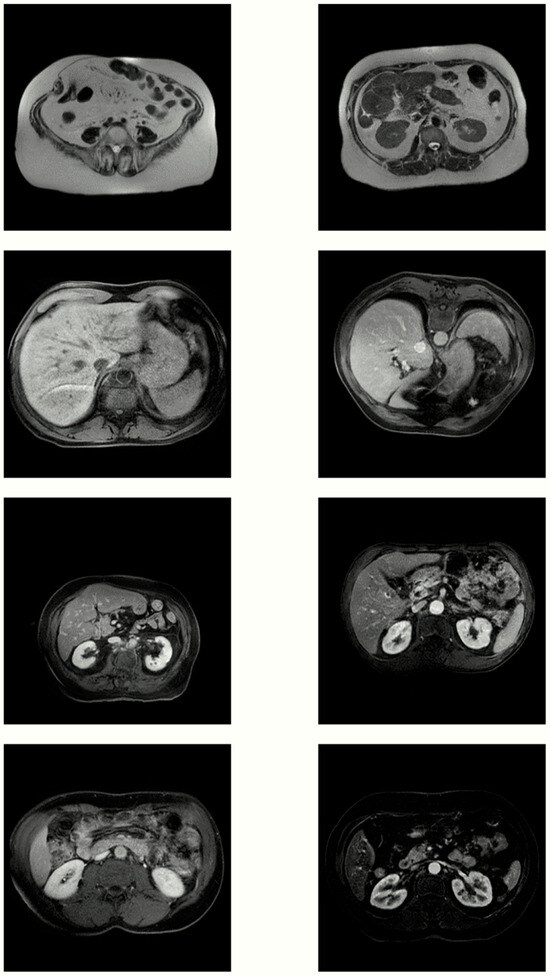

3.2. Visual Inspection

3.3. Medical Assessment